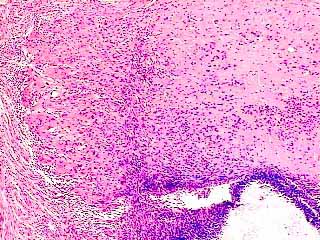

fig. 2

Figura 2. Mayor detalle del nódulo hialinizado en la superficie endocervical, en donde as aprecia también metaplasia tubaria del epitelio endocervical. H&E 100x